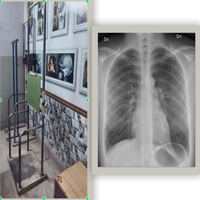

X ray chest stand

It is a fast and common procedure used to help diagnose conditions like pneumonia, a persistent cough, chest pain, or injury, and to monitor existing lung diseases like emphysema.

The test is simple, requires little preparation, and shows different tissues as varying shades of white, gray, and black depending on how much radiation they absorb.